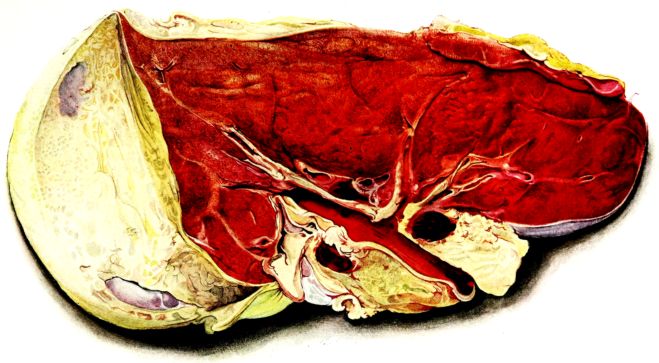

FIG. I. AUTOPSY NO. 99. ACUTE HEMORRHAGIC AND ULCERATIVE LARYNGOTRACHEITIS.

FIG. I. AUTOPSY NO. 99. ACUTE HEMORRHAGIC AND ULCERATIVE LARYNGOTRACHEITIS.

Early in the disease the congestion and the hemorrhages that have been described in the mucous membrane of the nasopharynx (14 and 94) are also conspicuous features in the lining of the trachea and bronchi (Fig. I). This membrane is swollen, turgid, red, and covered by a copious, mucous exudate which may be clear, but much more frequently is blood-stained or opaque and yellowish in color. The blood, variable in amount, may be fresh and red; and after the mucous exudate on the surface is removed, more intense red foci stand out on the congested base (47, 90, 157). Frequently, as the bronchi are approached, the red color of the mucosa becomes more intense and may have a garnet tinge. Membranes such as are encountered in the more usual necrotizing inflammatory processes, like diphtheria, have not occurred in the trachea and larger bronchi in this series (108, 128, 157).[3] The exudate peels off readily, and as indicated above, leaves a velvety red surface, 14dotted here and there with darker or more intensely red foci. Small ulcerations of the mucosa occur, but are inconspicuous (82, 156). As the finer ramifications of the bronchi are approached, the accumulation of the exudate in their lumina becomes more and more marked, and on cross section of the lung, they often stand out conspicuously on account of their increased size and projecting, seromucous, blood-stained content (101, 149, 162).